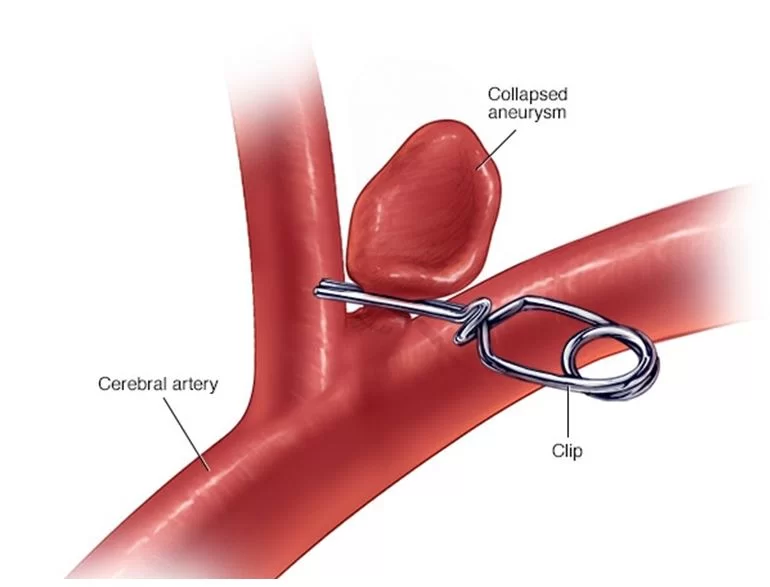

Στην περίπτωση του χειρουργείου, τοποθετείται χειρουργικά ένα κλίπ στον αυχένα του ανευρύσματος και έτσι το ανεύρυσμα δε μπορεί πλέον να γεμίσει με αίμα και καθίσταται ακίνδυνο (Εικόνα 4).